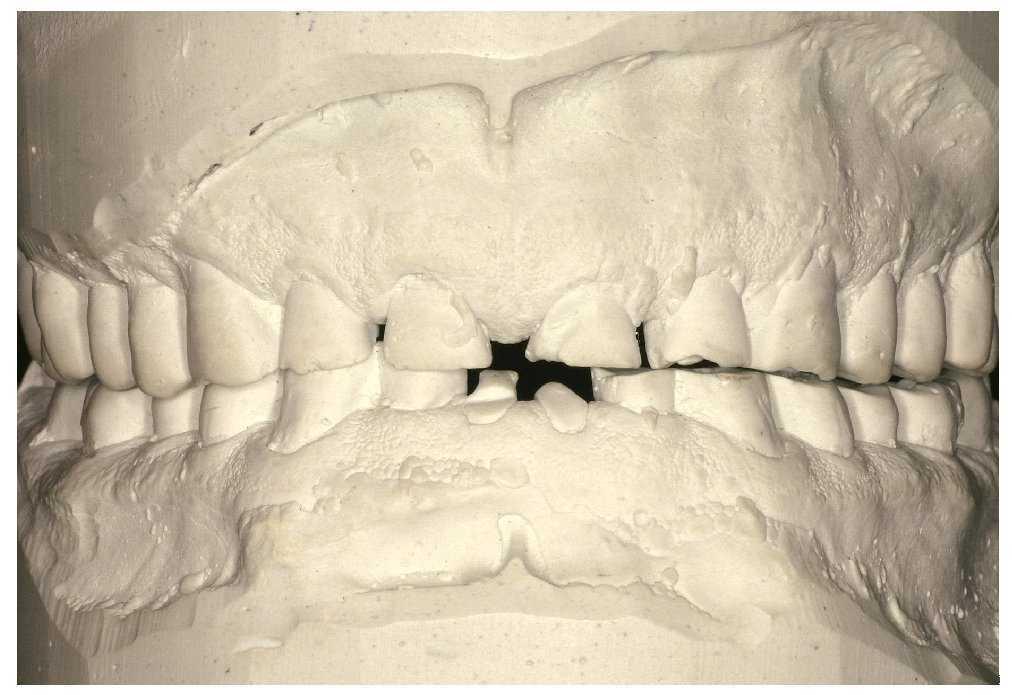

Destrucción de los tejidos duros dentarios más acusada en el sector anterior de ambas arcadas (fig. 3)

Figura 3. Destrucción grave de los tejidos dentales duros.